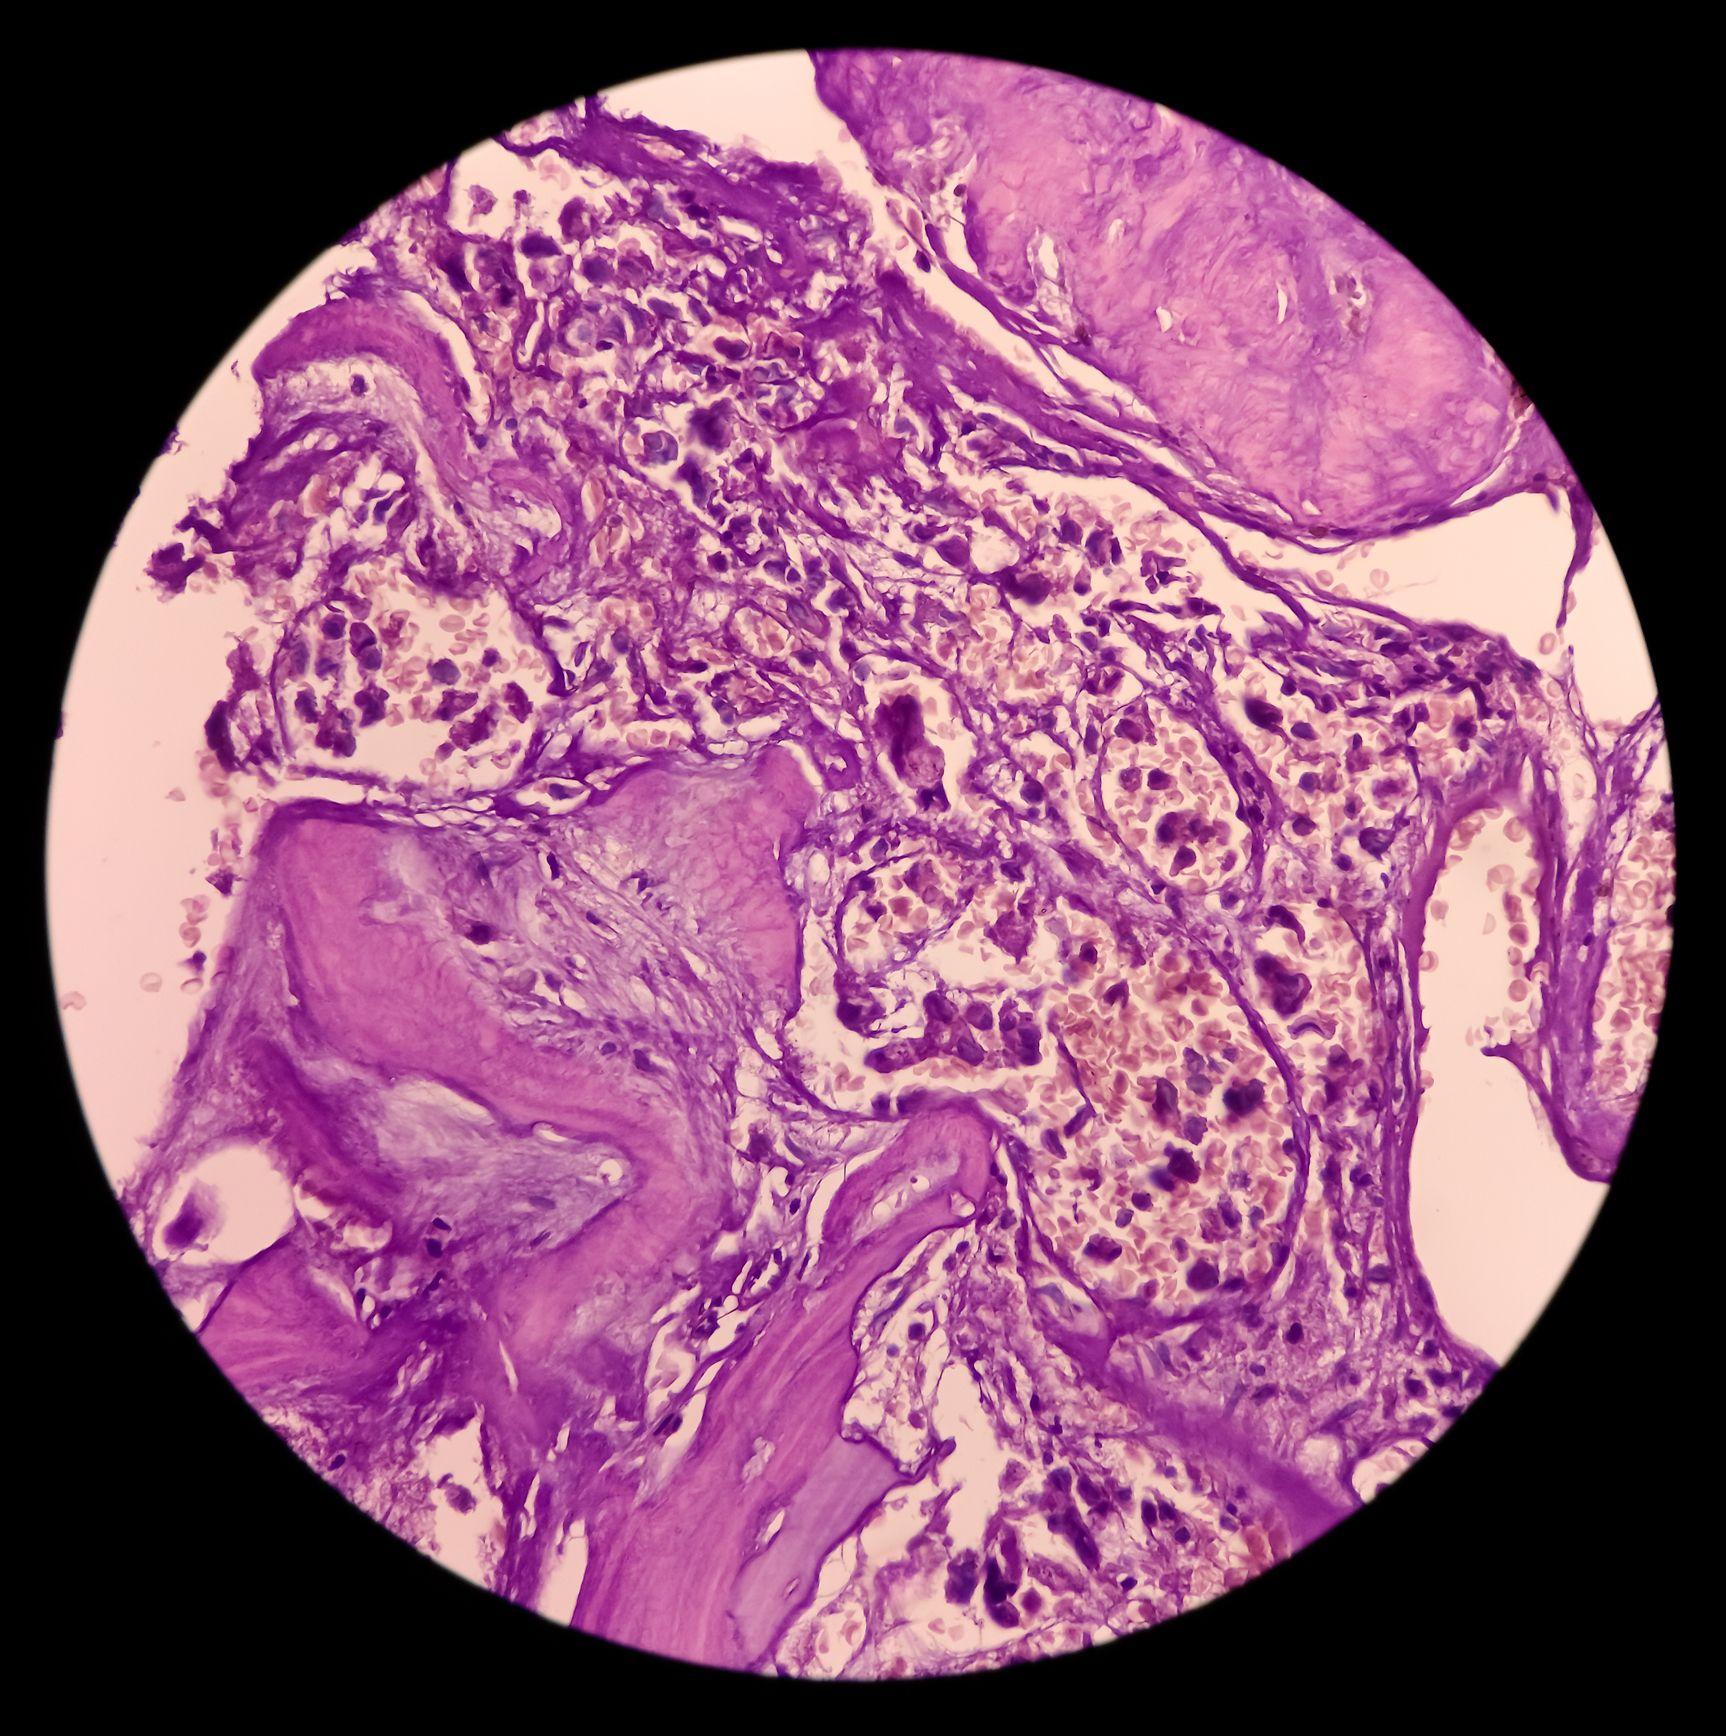

El cordoma es un tipo de cáncer de hueso muy raro y de crecimiento lento.

Los cordomas crecen a partir de la notocorda, que forma el tejido espinal temprano en el desarrollo del bebé en el útero.

Durante el desarrollo, la notocorda es reemplazada por hueso. Pero a veces, pueden quedar pequeñas áreas de notocorda en los adultos.

Aproximadamente 35 de cada 100 cordomas (35%) crecen en la base del cráneo y 50 de cada 100 (50%) en el hueso (sacro) entre los huesos de la cadera. El resto se desarrolla en los huesos de la columna.